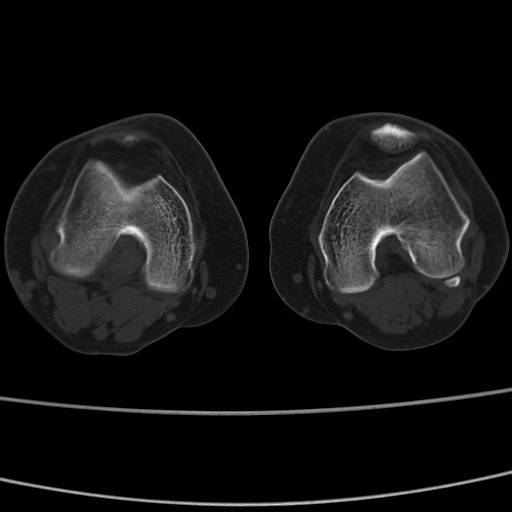

女性,50岁。【请提供患者临床症状体征】

右膝关节退行性改变,关节游离鼠。

右膝关节退行性改变,滑膜黏液囊钙/骨化并游离。